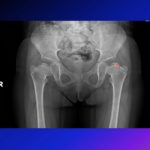

Courtesy: Dr Sally Hobson, Hull Royal Infirmary, Hull, UK

Herring (Lateral Pillar) Classification

This classification is based on the preservation of the lateral pillar of the femoral head epiphysis on anteroposterior radiographs during the fragmentation stage.

Herring Classification for Perthe’s Disease

Herring Lateral Pillar Classification

Group A: No involvement of the lateral pillar.

Group B: At least 50% of lateral pillar height maintained.

Group C: Less than 50% of lateral pillar height maintained.

To designate borderline groups between B and C the B/C border group was included.

- B/C1: lateral pillar more than 50% width, but < 2 to 3 mm width

- B/C2: lateral pillar more than 50% width, but little ossification

- B/C3: lateral pillar more than 50% width, but depressed relative to central column.